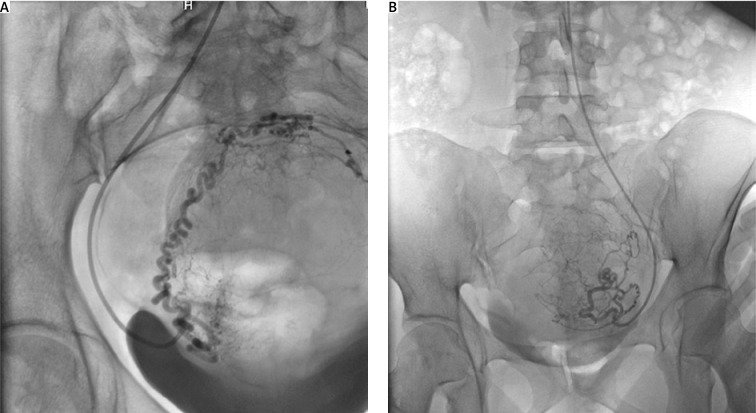

子宫动脉栓塞(UAE)是一种微创方法,已被证明是治疗症状性肌瘤的有效替代子宫切除术和子宫肌瘤切除术,尽管其对生育和产科结局的影响仍存在争议。本病例报告报告了一名31岁的未生育妇女,她有子宫肌瘤增大的病史(约为怀孕16-20周的大小),她接受了UAE治疗,怀孕并通过剖宫产生下了健康的孩子。在35岁时,由于症状复发,进行了第二次阿联酋手术,随后成功受孕并分娩了第二个孩子。本报告探讨了临床过程、管理策略和多学科方法在取得成功结果中的作用。尽管文献中已经积累了大量关于UAE作为子宫肌瘤非手术治疗选择的安全性和有效性的证据,但该手术对未来生育和产科结局的影响仍存在疑问,包括流产、前置胎盘和早产的风险。子宫动脉栓塞是一种有希望的微创替代子宫肌瘤切除术的妇女谁想要保留其生育能力的肌瘤。本病例表明,成功的受孕和分娩是可能的,当患者接受密切的随访和个性化的管理。

Uterine artery embolization (UAE) is a minimally invasive method that has been proven to be an effective alternative to hysterectomy and myomectomy for the treatment of symptomatic fibroids, though its impact on fertility and obstetric outcomes remains controversial. This case report presents a 31-year-old nulliparous woman with a history of fibroid-enlarged uterus (about the size of a 16-20-week pregnancy), who underwent UAE treatment, became pregnant, and delivered a healthy child by cesarean section. At the age of 35, a second UAE was performed due to recurrence of symptoms, followed by a successful conception and delivery of a second child. This report explores the clinical course, management strategies and the role of a multidisciplinary approach in achieving successful outcomes. Although substantial evidence has accumulated in the literature about the safety and effectiveness of UAE as a non-surgical option for uterine fibroids treatment, this procedure still raises questions about its impact on future fertility and obstetric outcomes, including the risk of miscarriage, placenta previa, and preterm delivery. Uterine artery embolization is a promising minimally invasive alternative to myomectomy for women with fibroids who want to preserve their fertility. The present case demonstrates that successful conception and childbirth are possible when patients undergo close follow-up and individualized management.